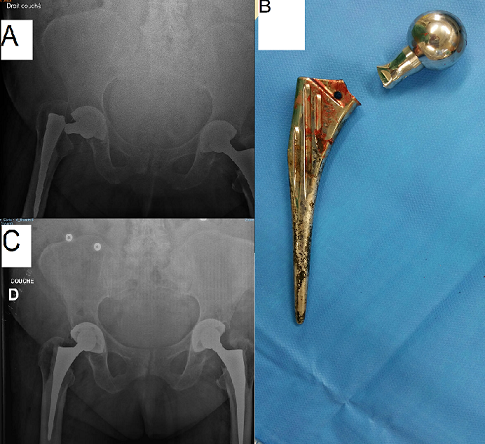

Il s'agit d'un patient âgé de 82 ans, opéré il y a 15 ans pour coxarthrose de la hanche gauche pour laquelle il a bénéficié d'une prothèse totale de hanche avec une bonne évolution clinique et radiologique puis opéré il y a 10 ans pour le côté droit avec mise en place d'une prothèse totale de hanche. L'évolution était marquée au niveau du côté droit par la sensation des douleurs au niveau de la hanche avec une impotence fonctionnelle totale du membre inférieure gauche. L'examen clinique a permis de mettre en évidence un raccourcissement du membre inférieur droit estimé à 4 cm, avec une attitude en adduction et rotation externe. La radiographie du bassin a objectivé un descellement de la prothèse de hanche par fracture de la tige fémorale au niveau du col (A). Le patient a été réopéré pour ablation de la prothèse fracturée (B) et son changement par un autre type de prothèse cimentée. La radiographie de contrôle a montré une bonne position de la prothèse avec correction de la longueur du membre inférieure droit (C). Les suites post-opératoires étaient simples, avec une reprise de la marche et disparition des douleurs après 10 séances de rééducation.